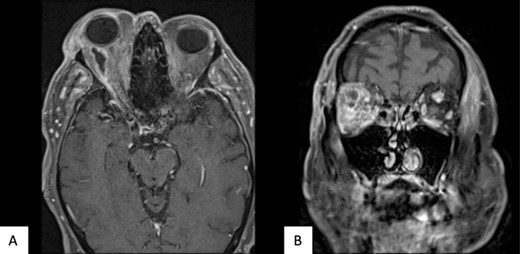

The patient underwent transconjunctival peritomy and drainage of the inferomedial abscess. However, vision regressed from hand movements to no light perception 5 days following initial drainage. Re-imaging of the orbit revealed a new retroorbital abscess accumulation superior-temporally (Fig. 4) that was also then drained. Both collections contained frank pus, and cultures also grew methicillin sensitive S. aureus, requiring a prolonged course of intravenous flucloxacillin and oral steroids. Subsequent MRI showed right lateral retroorbital abscess regression and less prominent retroorbital phlegmonous changes (Fig. 5). However, vision did not return to the patient’s eye.

(A) MR Orbit T1 TSE R TRA. (B) MR Orbit T2 FS TSE TRA. The right lateral retroorbital abscess has reduced in size. The traction on the optic nerve has reduced.